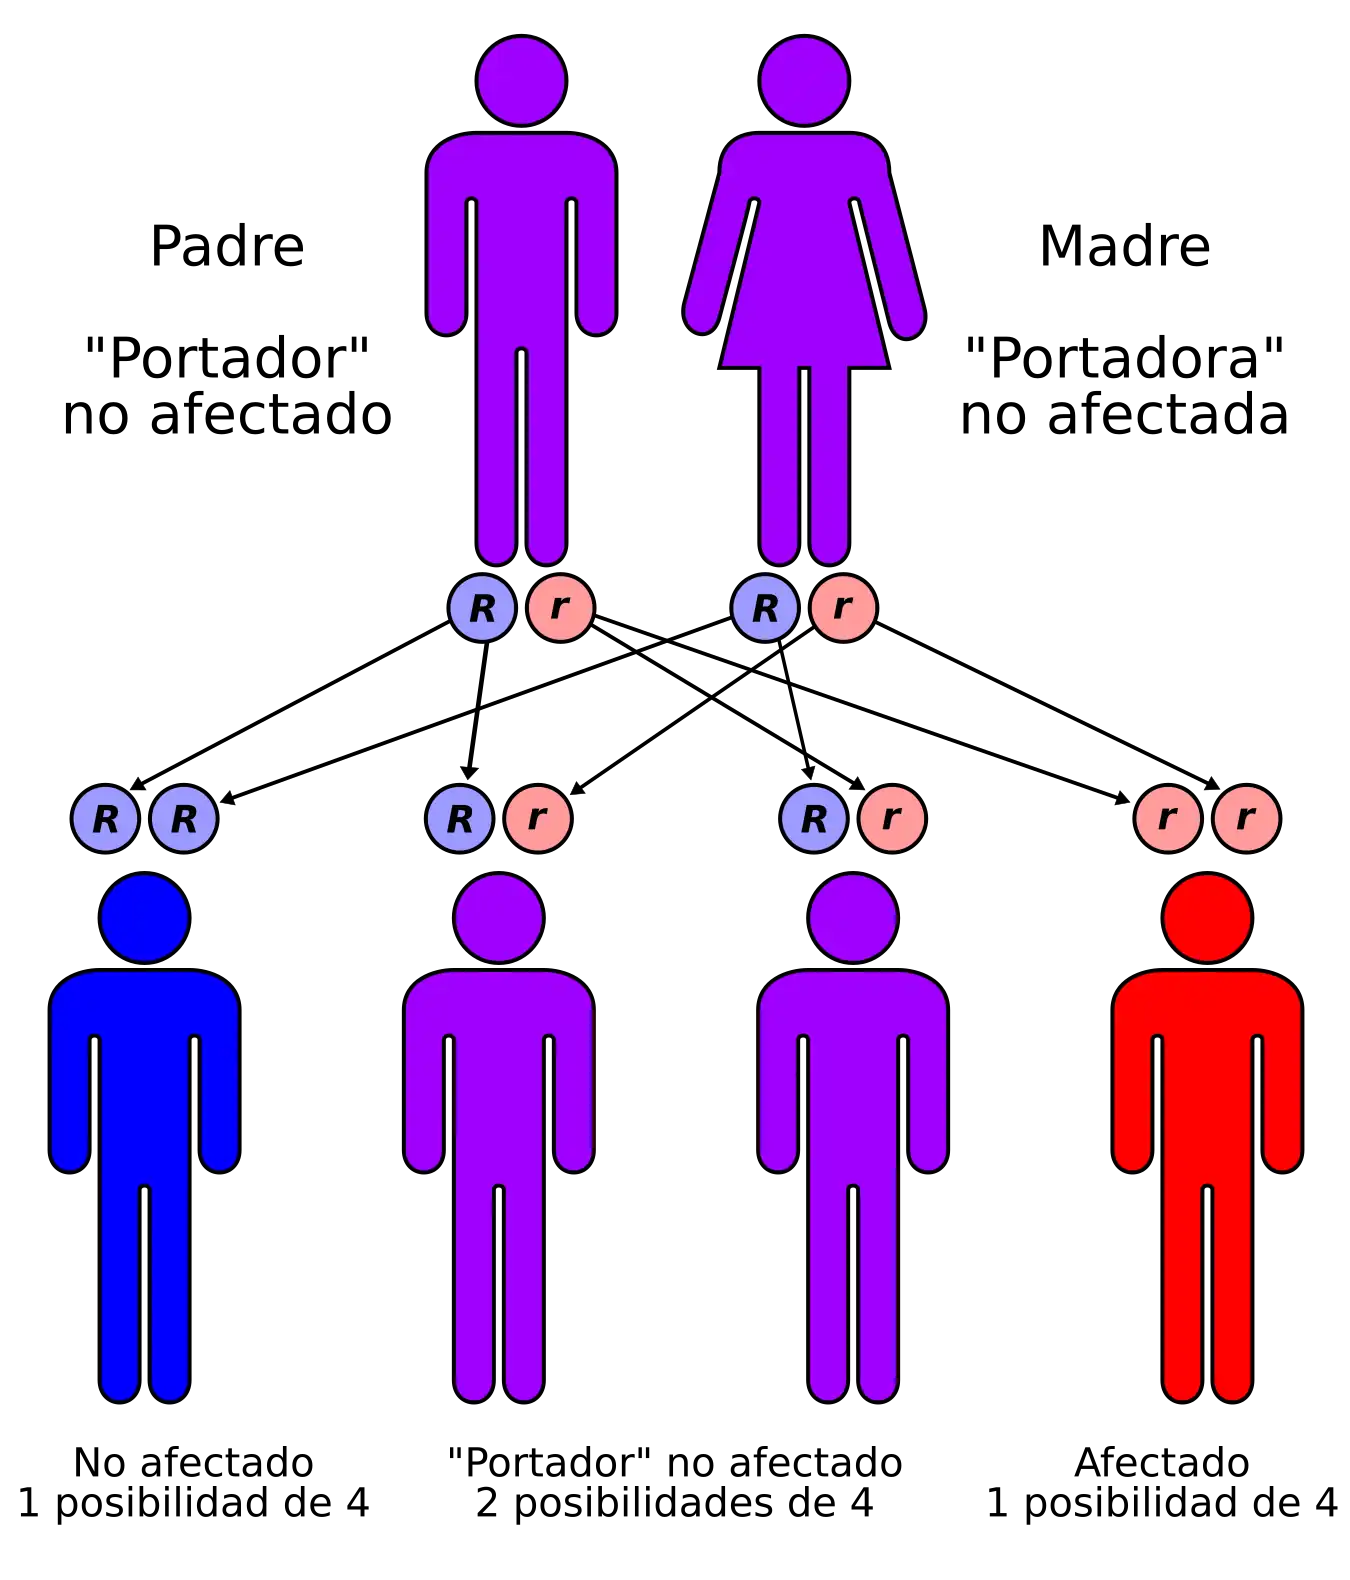

La enfermedad de Urbach-Wiethe (También conocida como proteinosis lipoidea y hialinosis cutis et mucosae) es una enfermedad genética , transmitida con un patrón autosómico recesivo, poco frecuente, con 400 casos conocidos desde su descubrimiento[1][2][3] Erich Urbach y Camillo Wiethe informaron oficialmente de ella por primera vez en 1929[4][5] aunque se pueden encontrar casos que se remontan a 1908.[6][7][8]

Dado que es la enfermedad de Urbach-Wiethe es una afección autosómica recesiva, los individuos pueden ser portadores de la enfermedad sin mostrar síntomas. La causa de la enfermedad se de a la pérdida de función por la mutación del cromosoma 1 en 1q21, el gen de la proteína de la matriz extracelular 1 (ECM1).[12] Los síntomas dermatológicos se producen por la acumulación de material hialino en la dermis y el engrosamiento de la membrana basal de la piel.[9] La enfermedad de Urbach-Wiethe se diagnostica normalmente por sus manifestaciones dermatológicas clínicas, particularmente las pápulas perladas en los párpados. El descubrimiento de la mutación en el gen ECM1 ha permitido el uso de las pruebas genéticas para confirmar el diagnóstico clínico inicial. La tinción de ácido peryódico de Schiff (PAS) y la tinción inmunohistoquímica también pueden usarse para el diagnóstico[6][13]